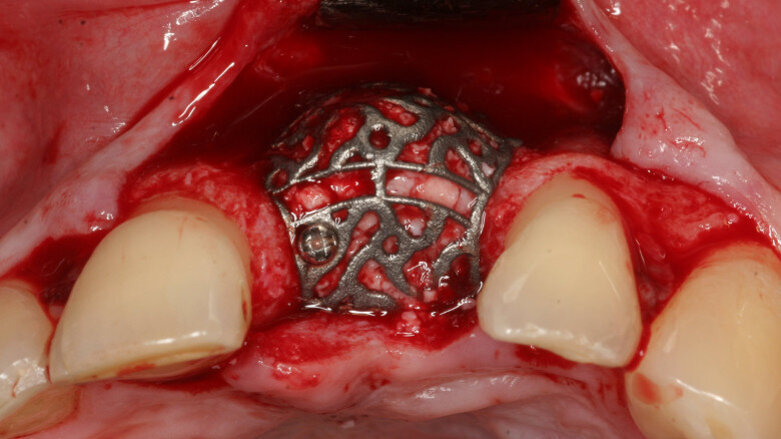

Computer-aided design/computer-aided manufacturing (CAD/CAM) technologies may improve application of titanium scaffolds, onlay techniques and guided bone regeneration. In this study, the clinical outcome of DICOM-based individualized CAD/CAM-produced titanium scaffolds (iCTSs) was analyzed in grafted defects, particularly with regard to relation of dehiscence to demographic and surgery-related factors.

Materials and methods: In 100 patients, 115 defects of the alveolar crest were reconstructed with an iCTS covered with a native bilayer collagen membrane or left uncovered. The volume was mostly grafted with a mixture of autogenous bone and deproteinized bovine bone mineral. The healing process was documented. Office records were analyzed for association of dehiscence with demographic and surgical parameters.

Results: Uneventful healing was observed in 82 defects. Infection of the surgical area was documented in 11 cases, 10 were resolved by medication. One defect had to be regrafted. Dehiscence was reported in 26 defects. Premature removal of exposed iCTSs was not necessary. All of the cases showed sufficiently grafted volume for implant placement with presurgical 3-D planning. The grafted volume in the defects with dehiscence did not differ from that in sites without dehiscence. Statistical analysis revealed no significant association of dehiscence with demographic or surgical parameters, but a tendency to higher prevalence of dehiscence with mesiodistal width of the defect.

Conclusion: Combination of an iCTS with guided bone regeneration offers a reliable grafting technique with low sensitivity to dehiscence. Dehiscence did not correlate with demographic or surgical factors. In addition, it did not affect the final outcome, as implant insertion was possible simultaneously or staged in all of the cases..